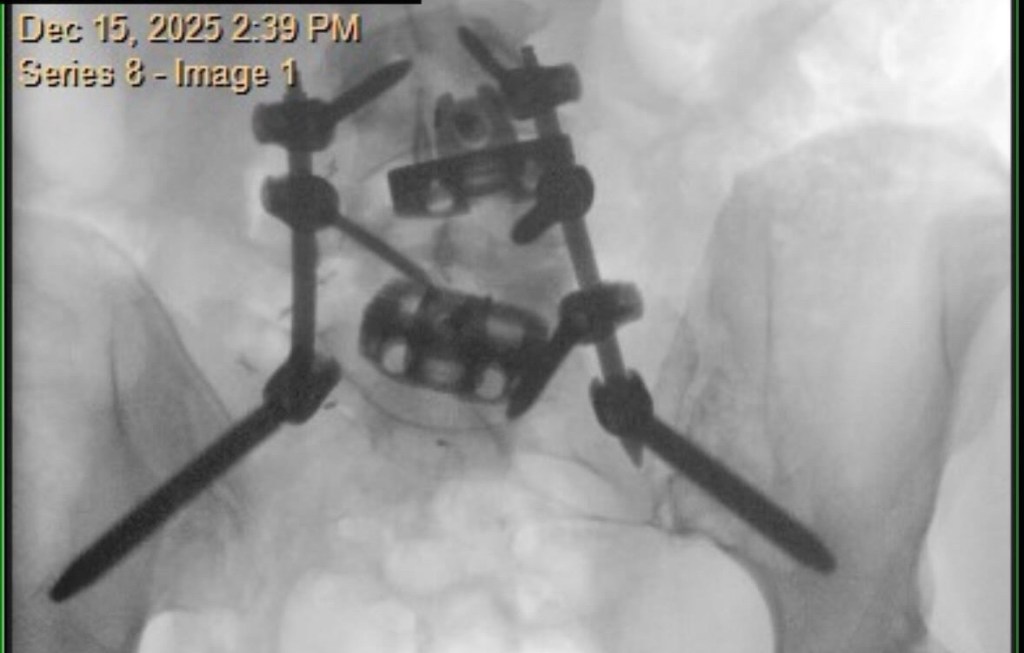

At my 3-month post-op appointment, my surgeon lifted all my restrictions and said I can return to all activity, “just listen to [my] body.” She measured my X-rays (above) and said my lumbar curve decreased 20 degrees, and the thoracic is the same. Also, I grew half an inch. I showed her the scoliosis program I found in New Hampshire, and she was all for it. I’ve booked a furnished apartment in New Hampshire 4/20-5/31 and scheduled the 12 sessions of treatment at the PT clinic there. I’m hopeful that will help with my back pain, and maybe even reduce my thoracic curve. And right before that, I’ll be attending Bionicon!